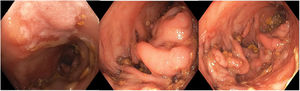

We present the case of a 73-year-old man with weight loss, abdominal pain, constipation, anaemia and rectal bleeding for months. Contrast-enhanced abdominal tomography was performed, revealing diverticula predominantly in the descending and sigmoid colon, with wall thickening and pericolonic fat stranding. A colonoscopy was performed, finding diverticula throughout the colon, and at the level of the sigmoid and descending colon, a significant stenosis of approximately 10 cm, with multiple ulcers and lesions with a vegetative appearance (Fig. 1). Biopsies taken from affected tissue only showed acute ulcerated inflammation and granulation tissue. Given the suspicion of neoplasia and obstructive symptoms, a left hemicolectomy was performed. In the macroscopic examination, multiple pseudopolypoid projections were observed (Fig. 2A and B). The histopathological report revealed extensively ulcerated and haemorrhagic segmental colitis associated with diverticulosis (Fig. 2C). Segmental colitis associated with diverticulosis (SCAD) is a chronic inflammatory process located in an area of diverticula, predominantly in the sigmoid.1,2 This presentation of SCAD is rare and can be confused with other pathologies.3 It is important to consider this diagnosis in patients with diverticular disease.